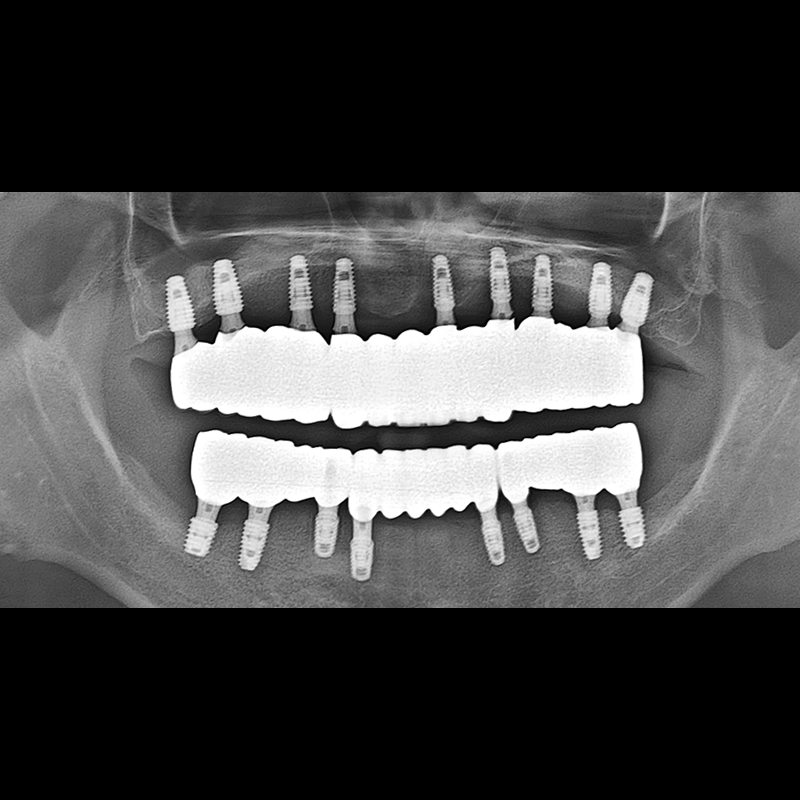

BEFORE AFTER

インプラント手術事例 2025.05.30

欠損した歯の部分と、生かしにくい歯の位置にインプラントを植立しました。